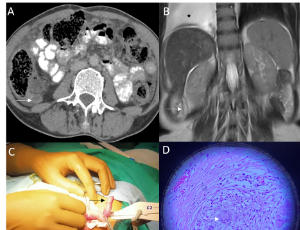

Superior mesenteric vein syndrome: A rare cause of duodenal obstruction mimicking SMA syndrome – Case report and surgical management

Background: Superior Mesenteric Vein (SMV) syndrome is an extremely rare cause of duodenal obstruction, resulting from external compression of the third portion of the duodenum by the SMV against the aorta. Due to its rarity and clinical similarity to Superior Mesenteric Artery (SMA) Syndrome, SMV syndrome may be misdiagnosed.

J Clin Exp Gastroenterol, 2025, Volume Volume 4, Issue Issue 1, p7-10 | DOI: 10.46439/gastro.4.023